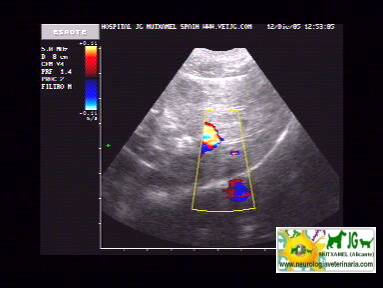

ecografía donde se aprecian las neoplasias hepáticas |

intentamos buscar el shunt portosistémico, pero no es visible ni con el doppler |

Se aprecia la vena porta muy aumentada de tamaño y sinuosa, por lo que es previsible que haya shunts, aunque no los distingamos |